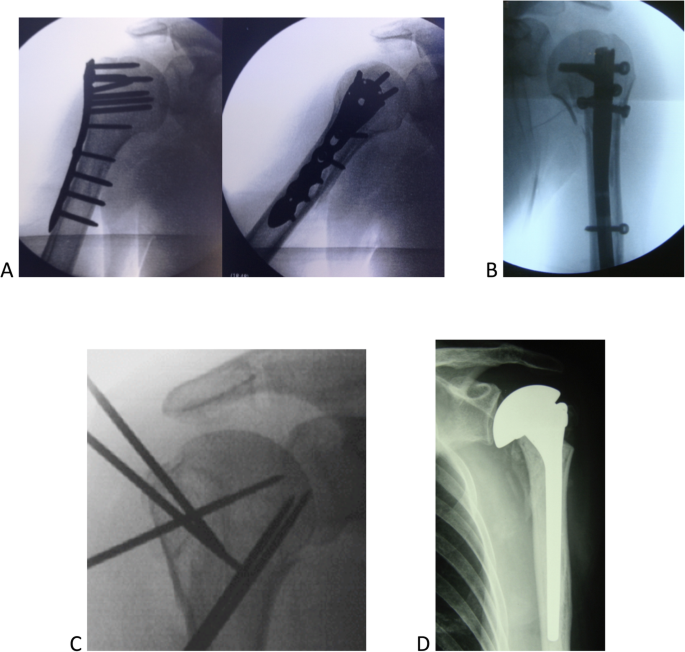

The work here assessed the correlation between different diagnostic methods, the indication of treatment, and the experience of the evaluator (experts and residents in orthopedics). We chose not to include clinical or epidemiological information of the nine cases studied (sex, age, dominance between limbs, associated diseases, fracture time or trauma mechanisms). In addition, we decided to keep aside the options between surgical and non-surgical treatments. The alternatives were widely presented as non-surgical or conservative, leaving out the use of slings or plastered immobilizations. The osteosynthesis and arthroplasty methods similarly did not indicate the types of surgical implants (locked plates, nails, wires, screws, models, or types of shoulder prostheses, Fig. 6 A,B,C,D). Therefore, the evaluators were presented with standardized treatment options: non-surgical, osteosynthesis, or shoulder arthroplasty.